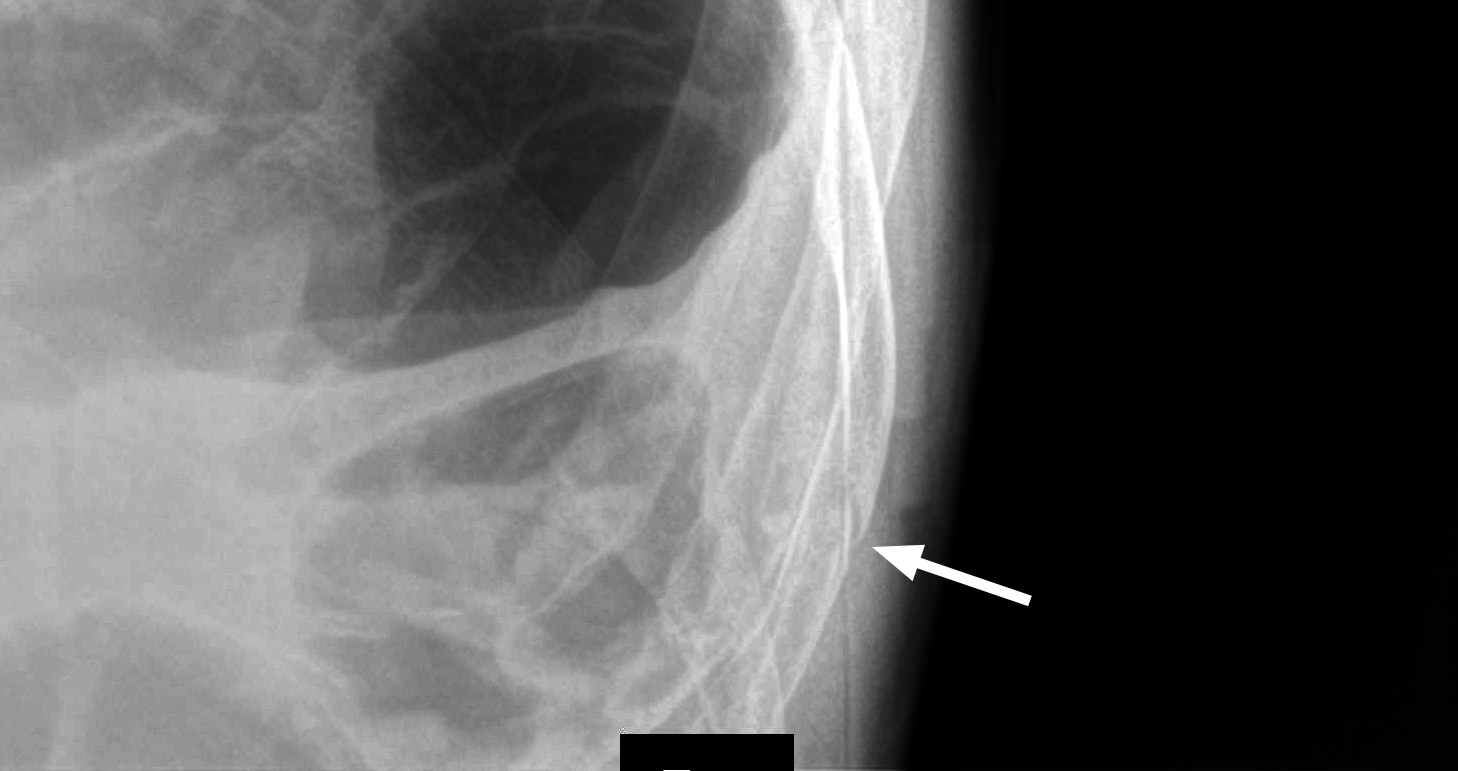

Свежий (1 день) перелом Х ребра слева.